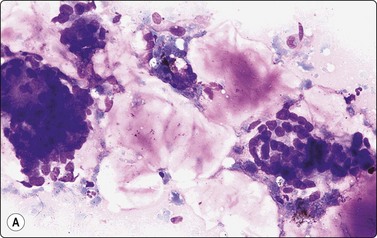

Squamous cell carcinoma (Figs 4.2 and 4.6)

Squamous cell carcinoma (SCC) is by far the commonest type of carcinoma encountered in the head and neck. Diagnostic criteria are listed in Chapter 8. Lymph node metastases of well-differentiated squamous carcinoma, particularly those arising in the Waldeyer’s ring, have a tendency to undergo liquefactive degeneration (see Fig. 4.3).41 The existence of primary SCC arising in a pre-existing branchial cyst has been doubted and is, in any case, an extremely rare event.42 The distinction from non-neoplastic cysts, mainly branchial cysts has been discussed above. Non-keratinizing squamous cell carcinoma may be represented in smears mainly by small basaloid cells in which case the differential diagnosis includes basal cell carcinoma, pilomatrixoma, poorly differentiated adenoid cystic carcinoma and other small cell tumors. Cells from a poorly differentiated squamous cell carcinoma have large vesicular nuclei and macronucleoli and resemble other anaplastic tumors such as melanoma and large cell lymphoma (Fig. 4.6).

image

Fig. 4.6 Squamous cell carcinoma

Mainly poorly differentiated malignant cells with large vesicular nuclei and large nucleoli; a few squamous and keratinized cells. FNB smears of cervical lymph node metastasis from squamous carcinoma of larynx (A, MGG; B, Pap, HP).